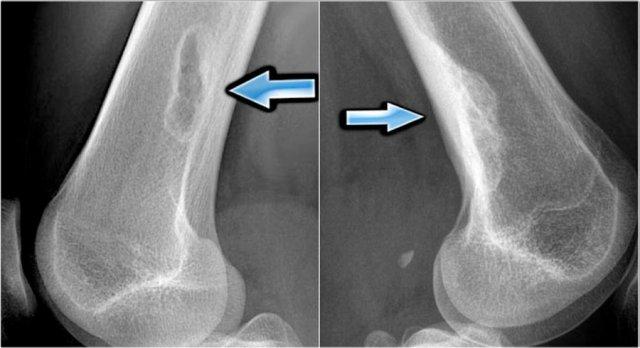

Các hình ảnh bên trái cho thấy một NOF tiêu xương điển hình với bờ xơ cứng rõ nét.

Hình ảnh bên phải là của một bệnh nhân khác có NOF cũ đã được lấp đầy hoàn toàn.

Đây là phát hiện tình cờ về một số tổn thương xơ cứng lệch tâm ở đầu xa xương đùi.

These are inert filled-in non-ossifying fibromas.

No further examination is needed.